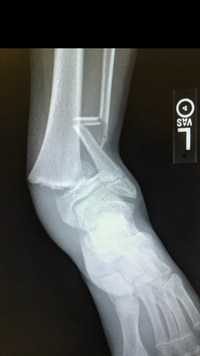

Takes me back to the time my kid, playing 15u baseball at 13 caught a bad throw to second, had to jump for it and got slid into upon landing. Dislocated, both bones broken, the big one right through the growth plate. He had a cast up to his crotch and was in a wheelchair.

He was good in a year. Concerns about his legs being different lengths because of the type of injury were thankfully just concerns. Full recovery. He was able to start at varsity short stop as a sophomore.